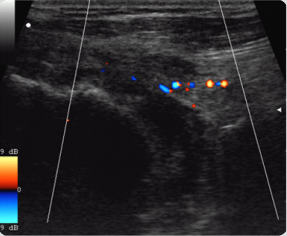

A complete rupture of the rotator cuff against the background of acute in-jury occurred in 64.8% of cases, against the background of chronic injury - in 35.2% of cases, respectively (P <0.05). The absence of tendon imaging in a typical place was detected in 70% of cases, while in the sonogram the humeral head contour was determined (70%) with adjoining the deltoid muscle (70%). Such an echographic picture corresponded to a massive rupture of a rotator cuff with damage to several tendons. In 96% of cases, complete rupture of the rotator cuff of the shoulder was accompanied by effusion in the subdeltoid-subacromial bag, in 90% of cases the effusion had a heterogeneous structure with hyperechoic inclusions, indicating the organization of the hematoma. In 57% of cases with identified effusion in the wall of the sub-deltoid-subacromial bag there was an increase in vascularization (Figures 1-4).

Figure 3: Echogram of hemorrhagic sub-deltoidsubacromial bursitis with a massive rupture of rota-tor cuff. Effusion heterogeneous structure with areas of the organization of hematoma (arrow).